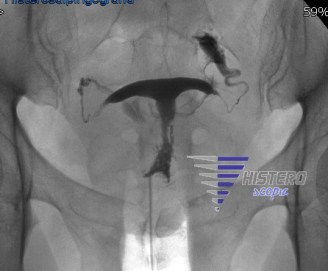

La cavidad uterina tiene habitualmente una forma triangular y es una cavidad amplia. Existen diversas variaciones en la forma de la cavidad, en el denominado utero en “T” o T-shaped uterus, esta cavidad adquiere forma de T, siendo la cavidad mas ancha en la parte superior y más estrecha, de aspecto tubular en la zona inferior, este estrechamiento se debe a la existencia de areas de fibrosis o anillos de constriccion a nivel del cuerpo uterino.

El diagnóstico suele hacerse mediante la ecografía, estos úteros habitualmente no tienen un buen desarrollo a nivel endometrial, permaneciendo generalmente con poco desarrollo o engrosamiento del mismo. La medida del volumen endometrial puede ser útil en el diagnostico de esta patología, estableciéndose el limite en menos de 6-7 mm en el día 10-14 del ciclo. La utilización de la ecografía tridimensional también puede ayudar en el diagnóstico. La prueba que más nos ayuda es la histeroscopia en la que se aprecia una cavidad tubular, sin espacio suficiente, en la que no se identifica una anatomía uterina normal.